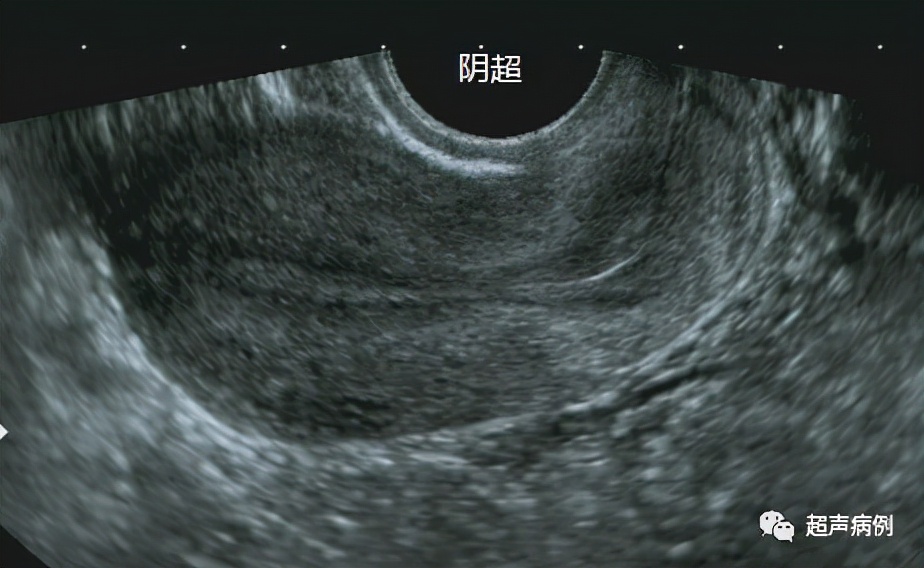

下图就是分别经腹部及经阴道超声的检查对比图。

可以看出经腹部的超声不能看清较小的卵泡及卵巢的细微结构,而经阴道超声就能看得清清楚楚。